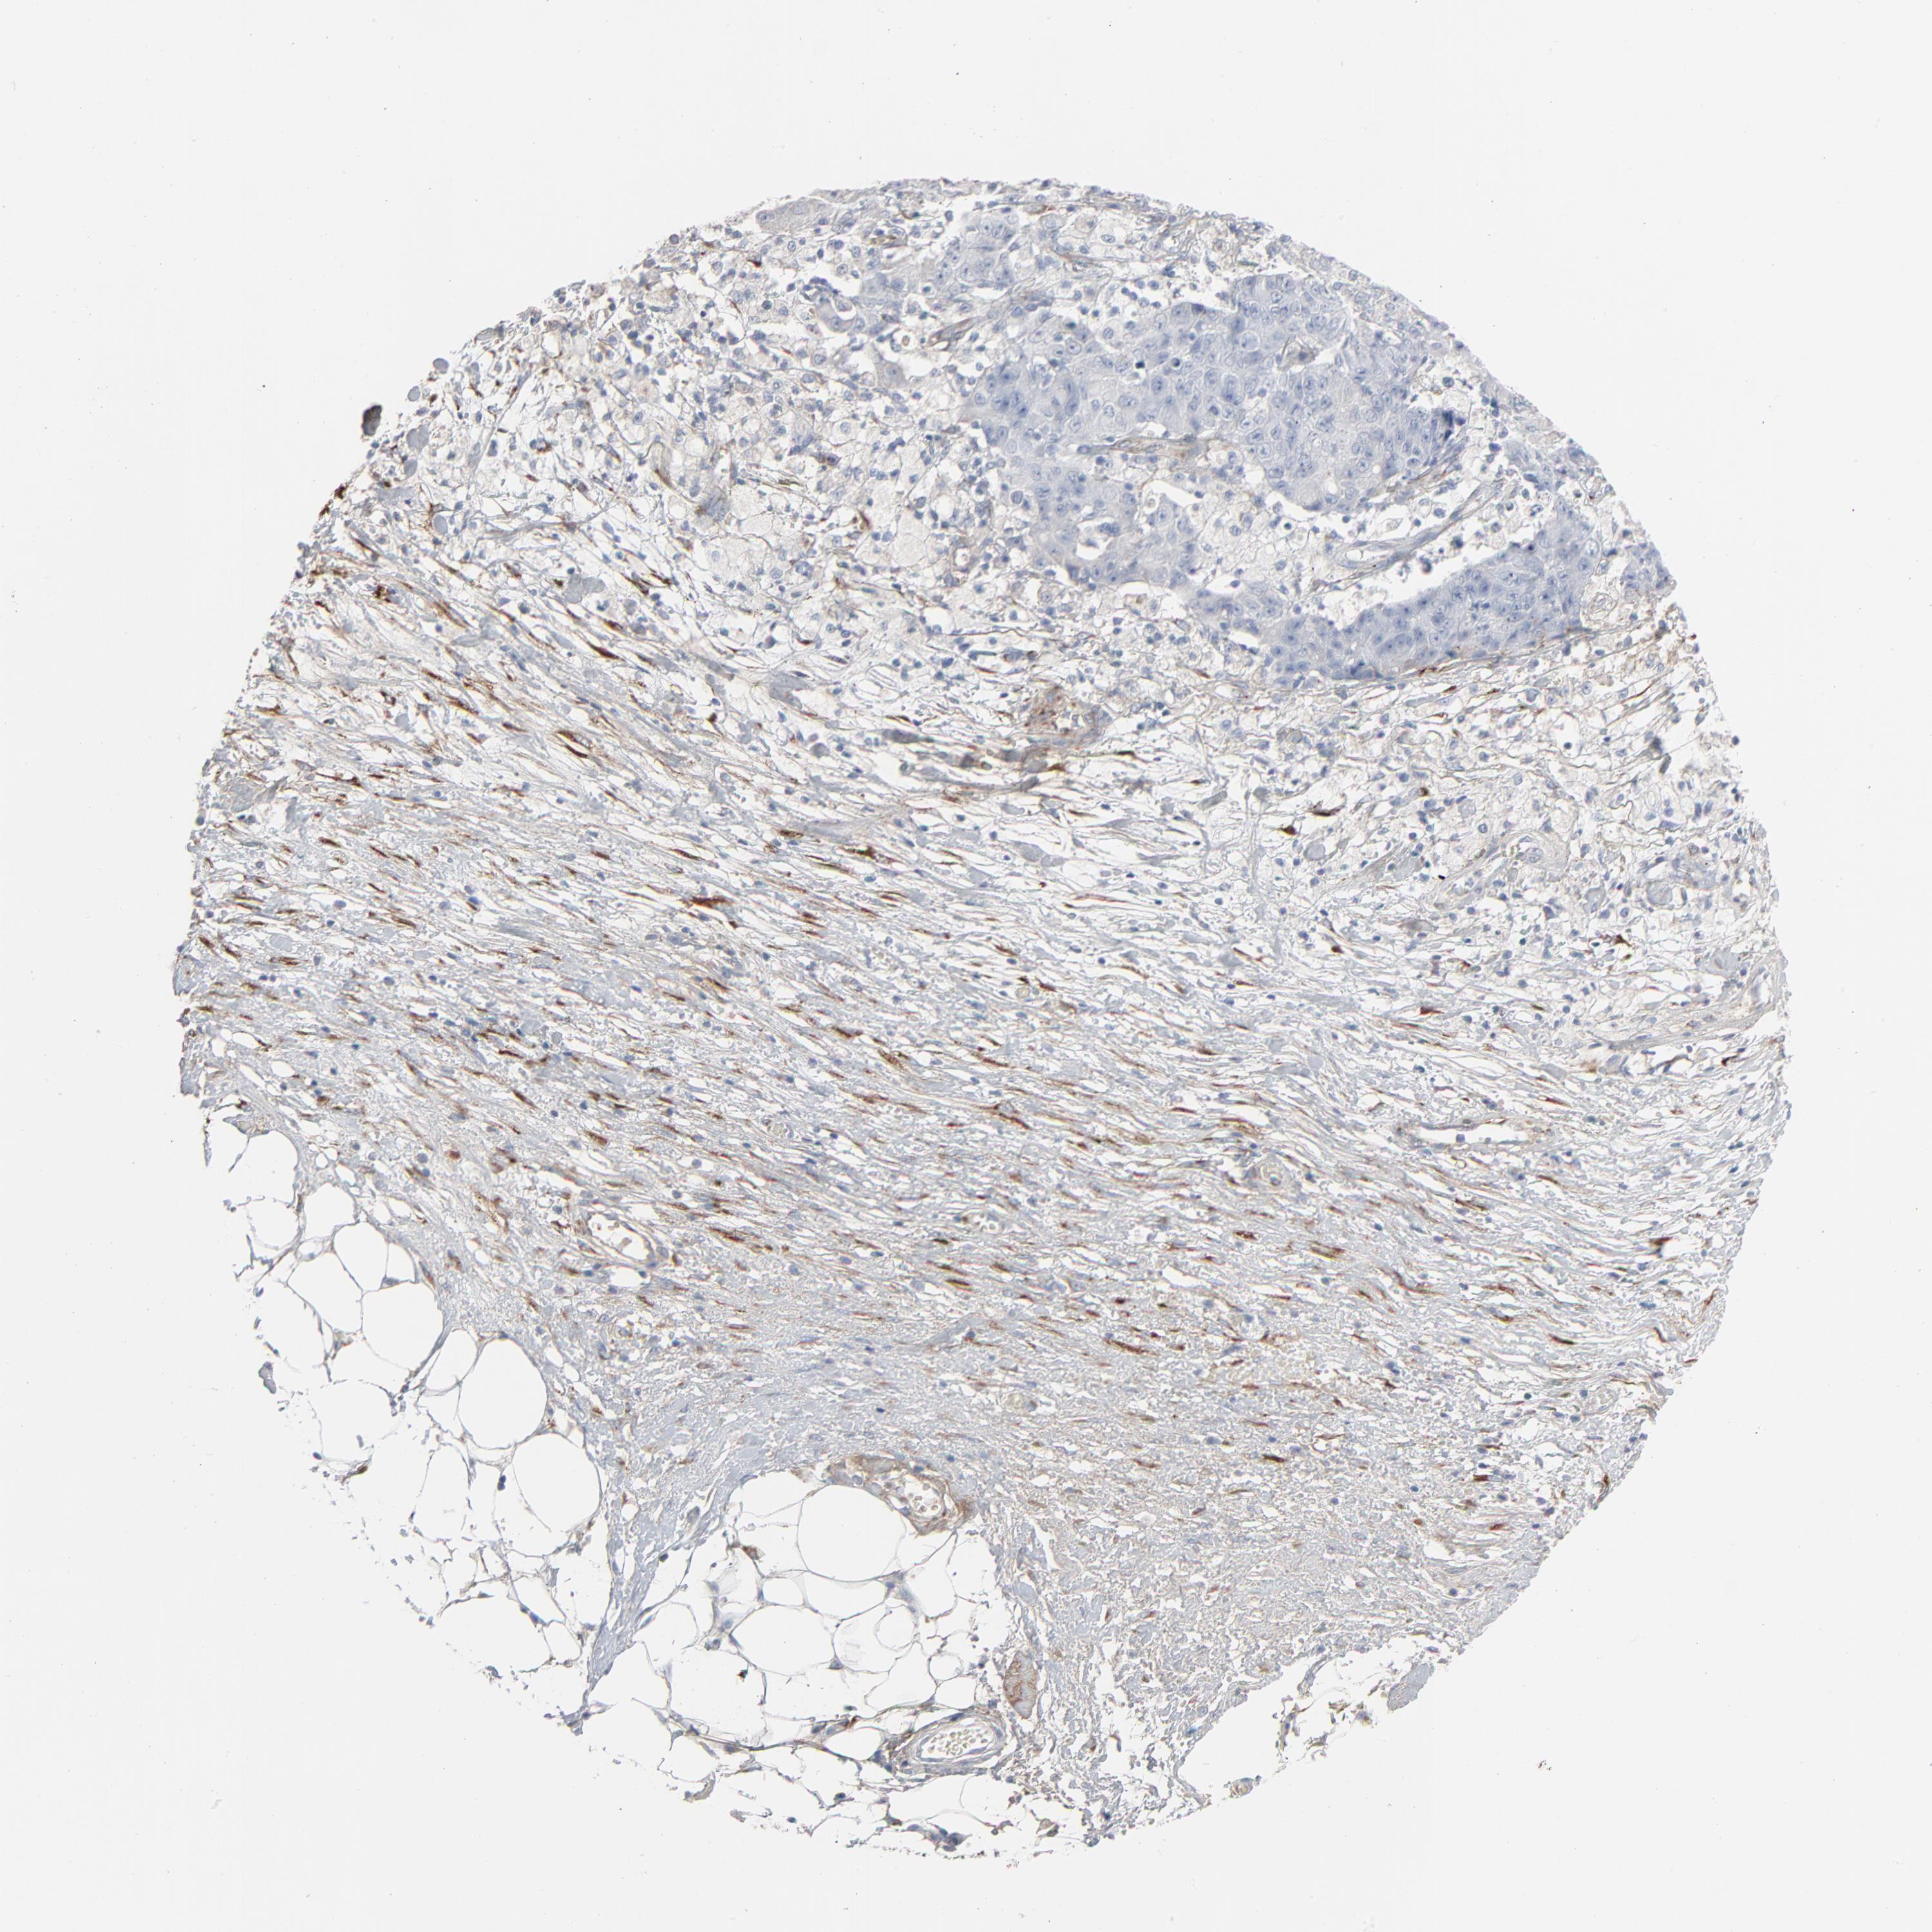

OVARIAN CANCER - Protein expressioni

A mouse-over function shows sample information and annotation data. Click on an image to view it in a full screen mode. Samples can be filtered based on level of antibody staining by selecting one or several of the following categories: high, medium, low and not detected. The assay and annotation is described here.

Note that samples used for immunohistochemistry by the Human Protein Atlas do not correspond to samples in the TCGA dataset.

Antibody stainingi

Antibody staining in the annotated cell types in the current human tissue is reported as not detected, low, medium, or high, based on conventional immunohistochemistry profiling in selected tissues. This score is based on the combination of the staining intensity and fraction of stained cells.

Each image is clickable and will lead to virtual microscopy that enables deeper exploration of all samples and also displays staining intensity scores, fraction scores and subcellular localization as well as patient and tissue information for each sample.

Antibody HPA003157

Antibody CAB003678

Carcinoma, endometroid

Cystadenocarcinoma, serous, NOS

Cystadenocarcinoma, mucinous, NOS